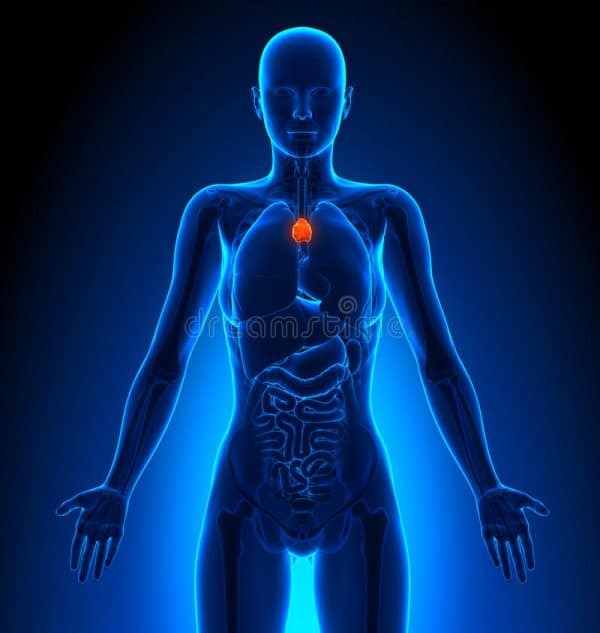

Τι είναι ο υποθυρεοειδισμός

- Ο θυρεοειδής αδένας είναι ένας μικρός αδένας σε σχήμα πεταλούδας που βρίσκεται κοντά στη βάση του λαιμού σας. Φτιάχνει και αποθηκεύει θυρεοειδικές ορμόνες που επηρεάζουν σχεδόν κάθε κύτταρο στο σώμα σας .

- Όταν ο θυρεοειδής αδένας λαμβάνει ένα σήμα που ονομάζεται θυρεοειδής ορμόνη (TSH), απελευθερώνει θυρεοειδικές ορμόνες στην κυκλοφορία του αίματος. Αυτό το σήμα αποστέλλεται από την υπόφυση, έναν μικρό αδένα που βρίσκεται στη βάση του εγκεφάλου σας, όταν τα επίπεδα των θυρεοειδικών ορμονών είναι χαμηλά .

- Ο θυρεοειδής αδένας δεν απελευθερώνει θυρεοειδικές ορμόνες, ακόμη και όταν υπάρχει άφθονο TSH. Αυτό ονομάζεται πρωτογενής υποθυρεοειδισμός και ο πιο κοινός τύπος υποθυρεοειδισμού.